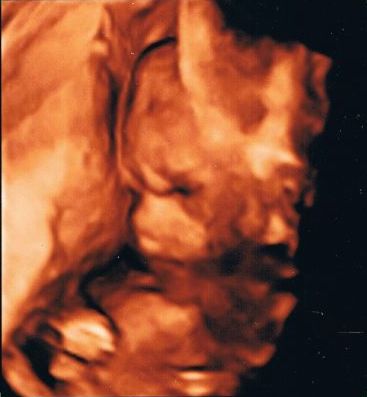

Ihr habt's ja so gewollt.

19. Woche, von Ende Januar.

3D??? -

4D sogar. Wobei ich nicht genau weiß, was die 4. Dimension tatsächlich ist. Vielleicht weil man sowas auch als Video aufnehmen lassen kann, glaube ich. (Würde aber wieder extra kosten :rolleyes)